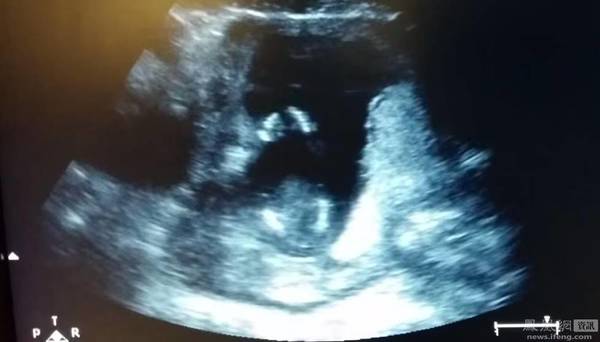

孩子在14周在肚子中动的样子。